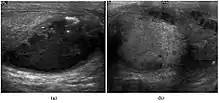

Fig. 21. Tuberculous epididymo-orchitis. (a) Transverse sonography of a surgically proved tuberculous epididymitis shows an enlarged epididymis containing calcification and necrosis. (b) Composite image: Transverse sonography of the same patient shows multiple hypoechoic nodules in the left testis associated with surrounding reactive hydrocele.

Although the genitourinary tract is the most common site of extra-pulmonary involvement by tuberculosis, tuberculous infection of the scrotum is rare and occurs in approximately 7% of patients with tuberculosis. At the initial stage of infection, the epididymis alone is involved. However, if appropriate antituberculous treatment is not administered promptly, the infection will spread to the ipsilateral testis. The occurrence of isolated testicular tuberculosis is rare. Clinically patients with tuberculous epididymo-orchitis may present with painful or painless enlargement of the scrotum, hence they cannot be distinguished from lesions such as testicular tumor, testicular infarction and may mimic testicular torsion.

At ultrasound, tuberculous epididymitis is characterized by an enlarged epididymis with variable echogenicity. The presence of calcification, caseation necrosis, granulomas and fibrosis can result in heterogeneous echogenicity [Fig. 21a]. The ultrasound findings of tuberculous orchitis are as follow: (a) diffusely enlarged heterogeneously hypoechoic testis (b) diffusely enlarged homogeneously hypoechoic testis (c) nodular enlarged heterogeneously hypoechoic testis and (d) presence of multiple small hypoechoic nodules in an enlarged testis [Fig. 21b].

Although both bacterial and tuberculous infections may involve both the epididymis and the testes, an enlarged epididymis with heterogeneously hypoechoic pattern favors a diagnosis of tuberculosis (Muttarak and Peh, 2006, as cited in Kim et al., 1993 and Chung et al., 1997). With color Doppler ultrasound, a diffuse increased blood flow pattern is seen in bacterial epididymitis, whereas focal linear or spotty blood flow signals are seen in the peripheral zone of the affected epididymis in patients with tuberculosis.